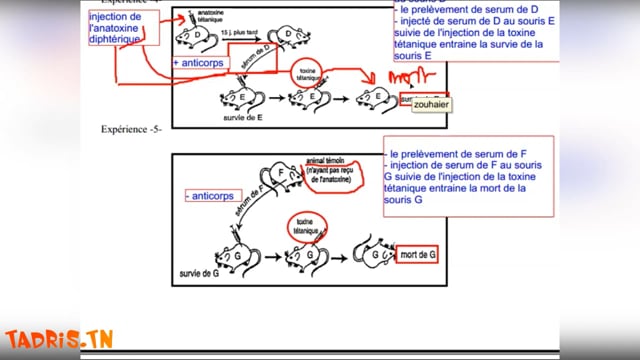

Sciences SVT